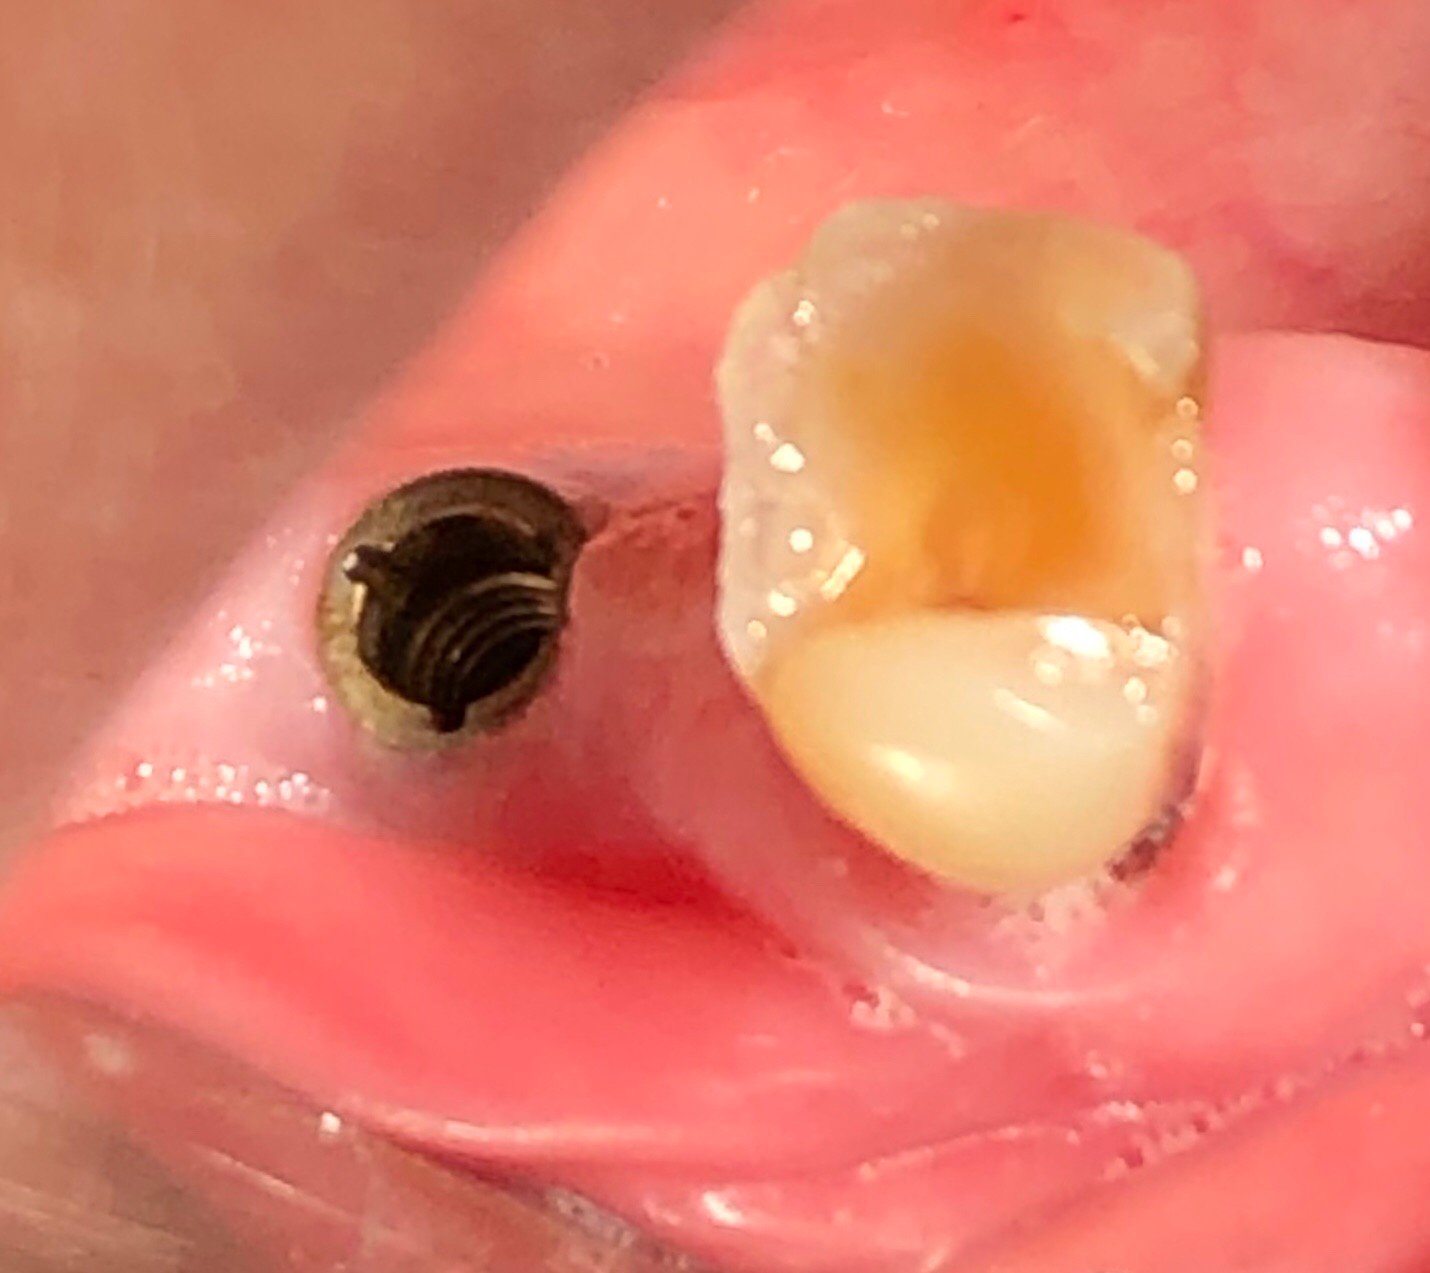

Me piden ayuda. No es mío. El implante es conexión externa y el cicatrizador se pudo quitar con el destornillador de Sweden&Martina. Ahora mismo no poseo más información. Espero que [...]